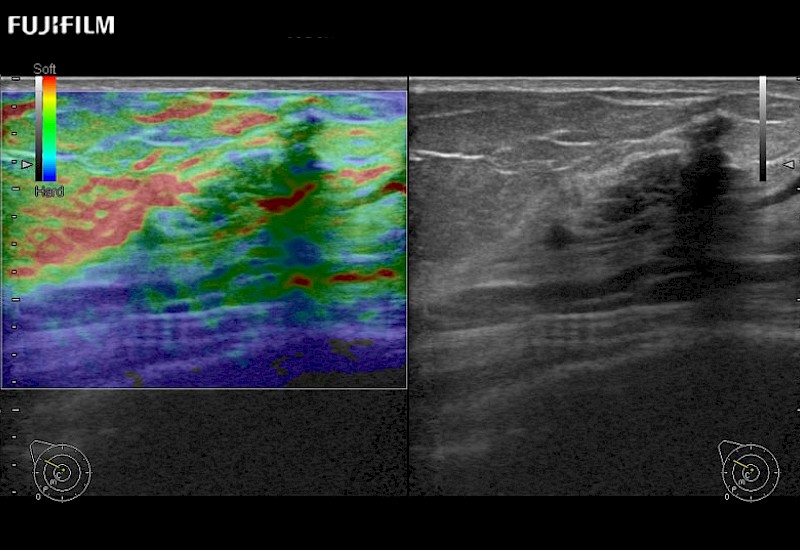

Multi-Parametric imaging modalities

Our dedication to Surgical Oncology allows us to offer superior image quality, outstanding system reliability and intuitive use of cutting edge technology.

- Instant feedback on tumor margin delineation

- Valuable information to guide tumor resections

The ARIETTA 750 incorporates all of the proven technologies and functions that medical professionals have come to expect from Fujifilm Healthcare.

ARIETTA 750 is the definitive diagnostic ultrasound solution for any clinical setting - Private Office, Imaging Center, or Hospital. The ARIETTA platform provides the ultimate in clinical performance with its state-of-the-art features and large user-friendly display.

The ARIETTA 650 DI combines trusted Fujifilm Healthcare technologies and features tailored for surgical oncology.

Designed to meet the demands of surgeons, the ARIETTA 650 DI offers precise guidance. Its advanced capabilities and large, intuitive display offer accurate and efficient care in operating rooms and specialized surgical settings.

Fujifilm Healthcare continues to listen to the experts, our neurosurgeons, by developing an ultrasound system specifically designed for the Operating Room.

Guidance is the fundamental purpose for all of our surgical ultrasound technology. Fujifilm Healthcare is committed to designing tools that help neurosurgeons navigate inside the human body and provide the necessary information to immediately make critical surgical decisions.

With the ARIETTA Precision the next level of surgical ultrasound is here.